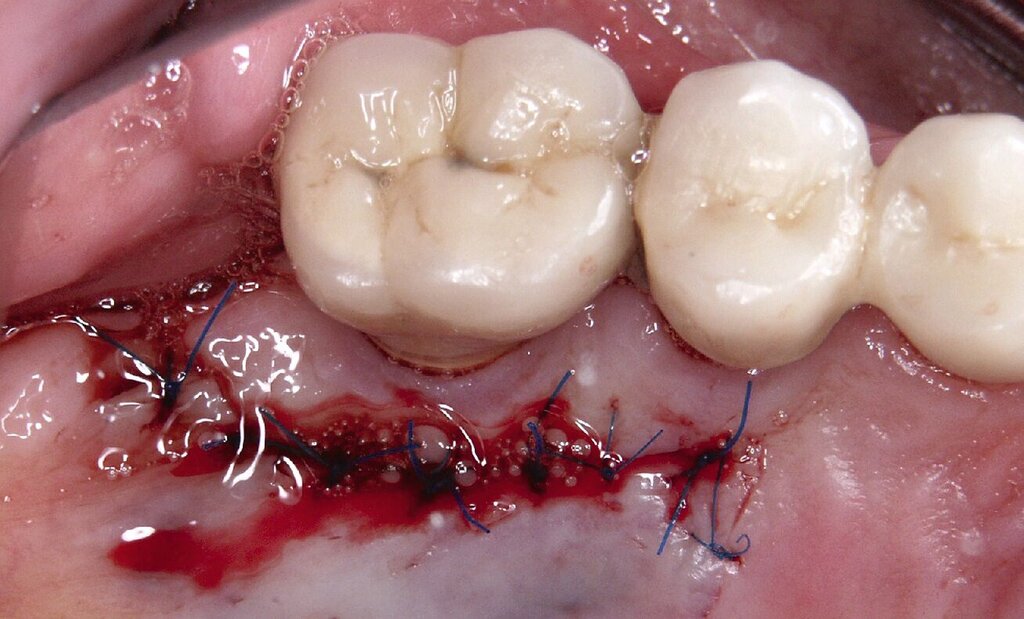

Eine präoperativ vorbereitete Interimsprothese, die über zwei gegossene Bonwill-Klammern sowie das verbliebene Implantat in regio 35 stabil abgestützt war, diente gleichzeitig als Verbandsplatte (Abb. 1f). Auf eine Glättung scharfer Knochenkanten oder die Nivellierung der Kieferkämme wurde verzichtet, um einen iatrogenen Knochenverlust zu vermeiden und das regenerative Potenzial des verbliebenen Knochens zu nutzen (Abb. 1g). Bereits bei der röntgenologischen Kontrolle nach drei Monaten war eine deutliche Zunahme des Knochens im Bereich der alten Implantatpositionen zu erkennen (Abb. 1h). Eine Nachimplantation von vier Implantaten in den Positionen 32, 34, 42 und 44 erfolgte neun Monate nach der Explantation und einer vorangegangenen Verbesserung der Weichgewebsbedeckung durch multiple freie Schleimhautransplantate vom harten Gaumen. Die knöcherne Regeneration unter der gut abgestützten Modellgussprothese verlief so günstig, dass sich der vertikale Höhenverlust des Alveolarkamms im Bereich der gescheiterten Implantate auf circa 2 mm begrenzen ließ. Das zur Entlastung der Kieferkämme und der einheilenden Implantate außerordentlich hilfreiche Implantat in regio 35 wurde erst nach dem Einheilen der nachgesetzten Implantate entfernt. Nach der Einheilzeit der Implantate von weiteren drei Monaten wurde eine kombiniert Zahn/Implantat-gestützte Teleskopprothese mit intraoral verklebten Galvano-Sekundärkronen eingegliedert (Abb. 1k bis 1m). Inzwischen ist diese, wie eine herausnehmbare Brücke abgestützte UK-Prothese seit zehn Jahren funktionstüchtig ohne Zeichen einer Periimplantitis an den vier Implantaten.

Da sechs Monate nach der Explantation keine nennenswerte knöcherne Regeneration festzustellen war, wurde eine zweizeitige Implantation nach Knochenaugmentation mithilfe dünner Knochenscheiben aus dem Kieferwinkel geplant. Die Entnahme erfolgte mit oszillierenden Instrumenten (Piezosurgery). Der Knochenblock wurde in dünne Scheiben geschnitten und mit Osteosyntheseschrauben am Alveolarfortsatz fixiert (Abb. 3e). Darüber wurden die Weichgewebe dicht vernäht. Weitere fünf Monate später erfolgte die Schraubenentfernung und die Implantation von zwei Bone-Level-Implantaten in regio 12 und 22 mit geschlossener Einheilung (Abb. 3f und 3g). Bei der Implantatfreilegung weitere sechs Monate später wurden die Weichgewebsdefizite im Brückengliedbereich durch ein kombiniertes Bindegewebs-/Schleimhauttransplantat aufgefüllt und gleichzeitig die keratinisierte periimplantäre Gingiva und Alveloarmukosa verbreitert (Abb. 3h und 3i). Die prothetische Versorgung erfolgte erst weitere drei Monate später, nach dem Konsolidieren der Weichgewebe. Die umfangreichen Augmentationsmaßnahmen konnten das transversale Weichgewebsdefizit vollständig kompensieren, während das verbleibende vertikale Defizit zu zervikal etwas längeren Kronen und Brückengliedern führte. Aufgrund der guten Abdeckung durch die Oberlippe kann das ästhetische Ergebnis als zufriedenstellend bewertet werden (Abb. 3j bis 3l).